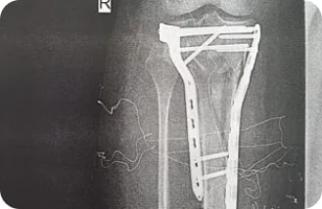

Остеосинтез перелома дистального метаэпифиза лучевой кости пластиной